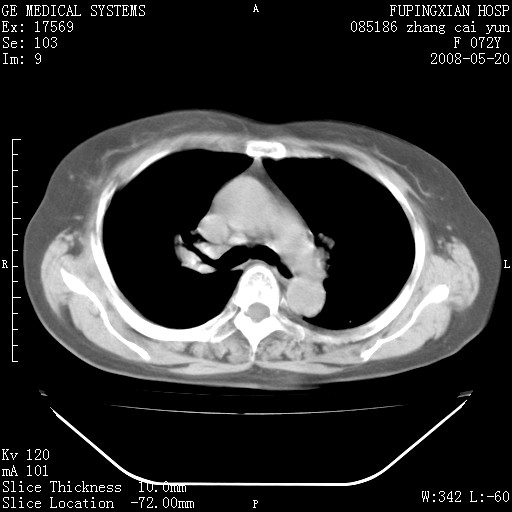

标题: CT13542:发热,咳嗽数日,经抗菌素治疗好转,请大家看排除 [打印本页]

标题: CT13542:发热,咳嗽数日,经抗菌素治疗好转,请大家看排除

右上叶支气管走行自然,未见明显管壁增厚等征像,另左主支气管起始部可见异常腔道向左侧延展左肺动脉干后方,与左下叶支气管相通,为左下叶支气管变异?

右肺上叶实变影,内见支气管充气征,右上叶支气管通畅,肺门区未见软组织密度影,抗炎治疗有效,考虑炎症,建议继续抗炎治疗复查。

右肺阻塞性肺炎  不除外支气管内膜结核

考虑为:右肺上叶感染性病变。建议:1)继续抗炎治疗后复查。2)必要时行纤支镜检查。

右肺上叶感染性病变。建议:1)继续抗炎治疗后复查。2)必要时行纤支镜检查。